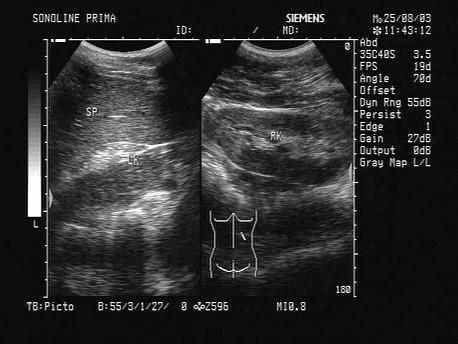

问题 如图所示,双肾结构清晰,左肾体积小,该病例最可能诊断是?(?)

选项 A.肾发育不良 B.肾萎缩 C.慢性肾炎 D.肾结核 E.慢性肾衰

答案 A